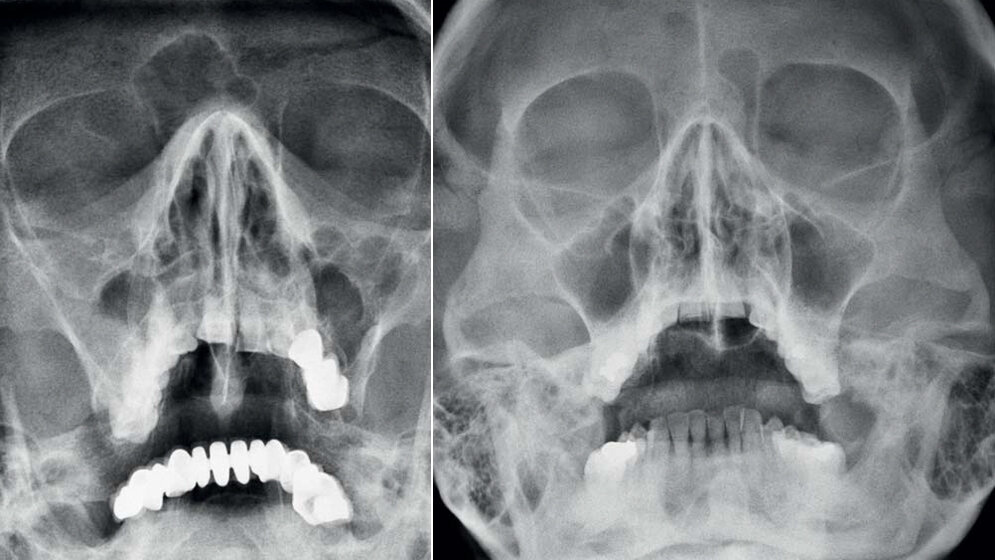

Die Nasennebenhöhlen sind paarige Strukturen und nach den Knochen benannt, in denen sie liegen. Im Alter von etwa 10 Jahren sind die paranasalen Sinus vollständig angelegt. Beim Metopismus ist die Inzidenz der Aplasie des Sinus frontalis erhöht. Die Aplasie beziehungsweise Dysplasie des Sinus frontalis oder sphenoidalis kann auch Teil anderer Malformationen sein.

The paranasal sinuses are paired structures and are named according to the bone from which they originate. By 10 years of age, all of the paranasal sinuses are developed. There is a low prevalence rate of the agenesis of frontal sinuses in dry skulls with metopism. The findings of aplasia/dysplasia of the frontal and or sphenoidal sinuses may be part of other malformations.